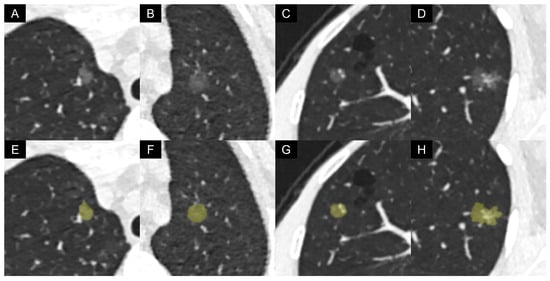

This AI software was integrated into the radiological diagnosis workflow side-by-side via connecting with the picture archiving and communication system (PACS). The output of the AI software included the maximal and minimum axial diameters, volume, attenuation, and mass of the nodule. The representative LDCT images and AI-based automatic segmentation results are presented in Figure 2. The diameter was the mean of the maximum axial diameter and the minimum axial diameter. The mass was calculated by the following equation [33]: Mass = Volume × (Attenuation + 1000)/1000. The units for diameter, volume, attenuation, and mass were mm, mm3, HU, and mg.

Figure 2. Representative low-dose CT images and artificial intelligence-based automatic segmentation results of pure ground-glass nodules: (AD) original images; (EH) segmentation results; (A,E) a 45-year-old female with non-invasive adenocarcinoma, with a vessel passing by the nodule; (B,F) a 74-year-old female with non-invasive adenocarcinoma, with a hazy boundary between the nodule margin and adjacent pulmonary parenchyma; (C,G) a 61-year-old female with invasive adenocarcinoma, with two dilated pulmonary vessels passing through the nodule; (D,H) a 47-year-old female with invasive adenocarcinoma, with irregular vascular dilation and vascular convergence within the nodule.